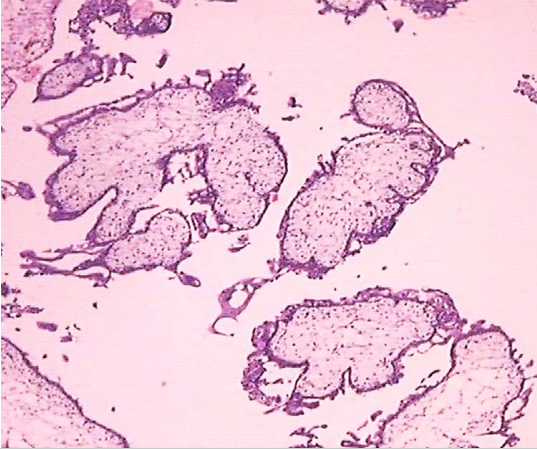

完全性葡萄胎大体观 完全性葡萄胎镜下观(100×)

见绒毛增大伴中央空没事形成及滋养细胞增生

2.部分性葡萄胎 仅部分绒毛呈水泡状,合并胚胎或胎儿组织,胎儿多已死亡,且常伴发育迟缓或多发性畸形,合并足月儿极少。镜下见:①有胚胎或胎儿组织存在;②局限性滋养细胞增生;③绒毛大小及其水肿程度明显不ー;④毛呈显著的扇贝样轮廓、间质内可见滋养细胞包涵体;⑤种植部位滋养细胞呈局限和轻度的异型性。完全性葡萄胎和部分性葡萄胎的核型和病理特征鉴别要点见表28-1。

部分性葡萄胎大体观 部分性葡萄胎大体观 部分性葡萄胎镜下观(100×)

中期妊娠,胎儿合并水泡状胎块。见大小不一绒毛,滋养细胞轻度增生